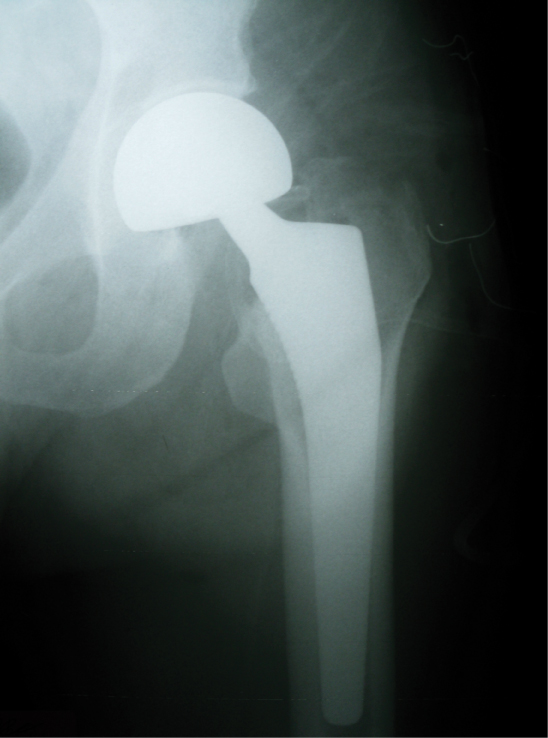

Next, a length of gauze was placed in the acetabulum, and the femoral canal was prepared by bringing the hip into flexion, adduction, and internal rotation, and where feasible by pushing toward the proximal femur incision. In some cases, the femoral neck had to be shortened with an electric saw. Then, the canal was reamed after placing two Hohmann retractors under the proximal femur. The trial reduction was made, generally by scraping, in some cases by placing the prosthesis and in doubtful cases by checking under fluoroscopy. After the canal was systematically washed and dried, the cement was applied then the prosthesis was put into place (Figure 1).

Figure 1: The intraoperative placement of the prosthesis in the mini-incision. View Figure 1

In all cases, a cemented prosthesis was applied. Then, bleeding was checked following reduction and tests. In all cases, the external rotators were repaired with sutures passing through the holes opened in the trochanter major. In addition, the capsule was repaired. After that, a hemovac drain was placed, and the layers were closed (Figure 2). Of note, a special retractor developed for mini-incisions was not used in any case. Figure 3 presents postoperative radiography of the case.

Figure 3: Postoperative view of radiography. View Figure 3